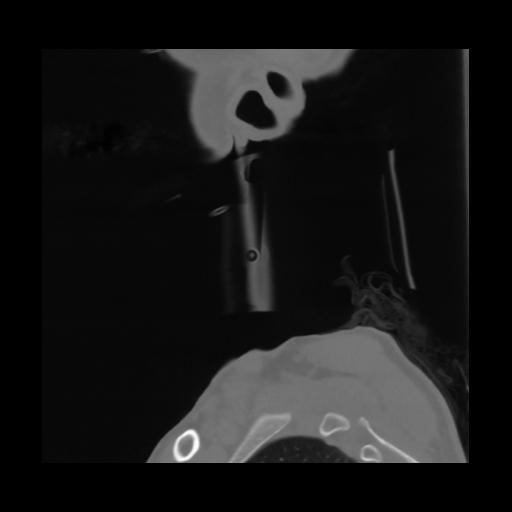

14 P.BLANDAS,,Sagittal,2.000,P.BLANDAS,Sagittal,